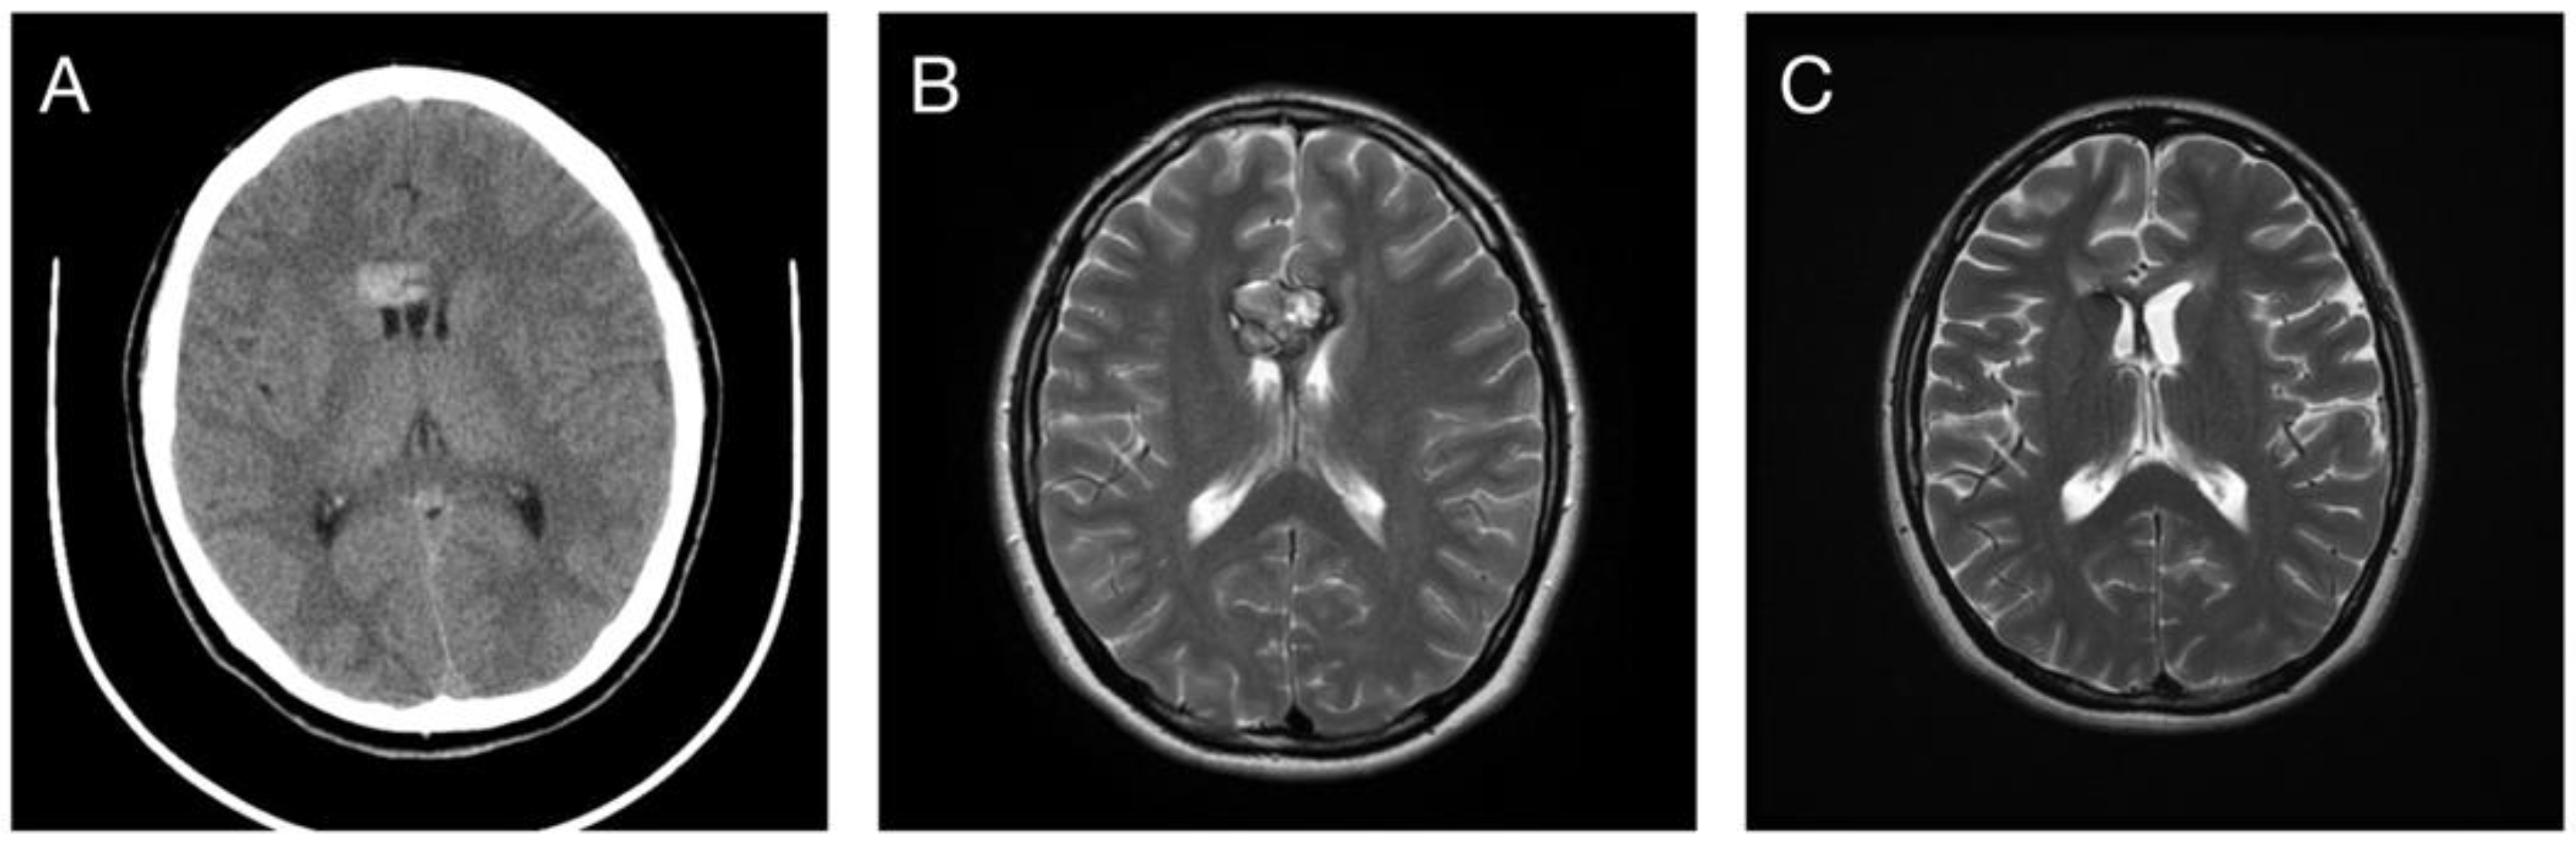

3.1. Patient Selection and Characteristics

3.3. Response in Volume Control